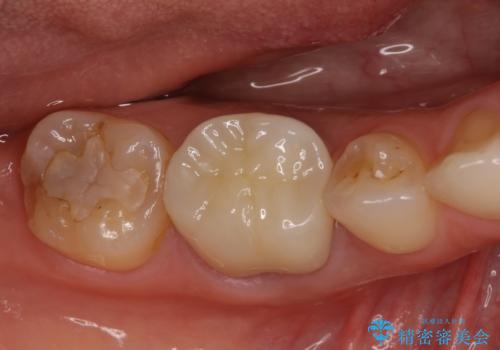

奥歯の深い虫歯をオールセラミックで治療